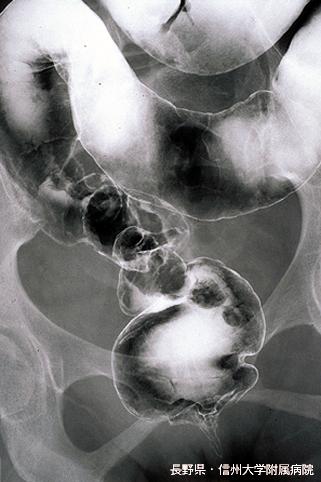

Posted by: Nagano Pref., Shinshu University Hospital (Dr. 赤松)

Barium enema reveals multiple elevated lesions in the rectum and the sigmoid colon, and poor contrast due to mucous discharge from the lesions.

Criteria of Hist.ClassificationInflammatory or ulcerative disease / lesions/Others

LocationLarge intestine(Colon)/More than one of the above

Technique, MethodX-ray

Size15 - 19